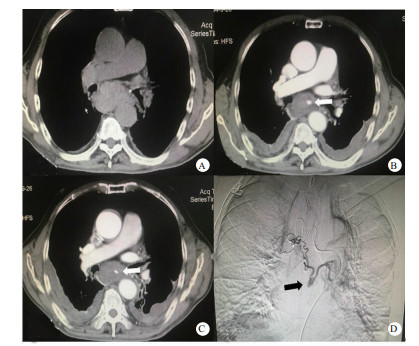

入院急诊心超示:升主动脉内径稍增宽。主动脉瓣反流(轻度)二尖瓣反流(轻度)。胸片示:右肺中叶感染性病变可能大,查胸部CT(图 1A)示:胸段食管不规则增厚,周边可见肿大淋巴结,建议胃镜及增强CT进一步检查。慢性支气管炎、肺气肿伴两肺感染,左肺支气管扩张,双侧少量胸腔积液。急诊医师予抗感染,化痰及减轻胃酸分泌等治疗后,患者胸痛未见好转,进一步查增强CT(图 1B)示:食管壁弥漫性水肿,围绕食管壁周围高密度影,考虑纵隔血肿形成,伴有活动性出血,联系介入科后行介入治疗,造影(图 1C)示:左右支气管动脉可见交通支,交通支可见假性动脉瘤表现,予行超选择性靶血管栓塞术。术后3 d复查胸部增强CT(图 1D)示:支气管动脉瘤破裂出血介入栓塞术后,纵隔血肿。较前纵隔血肿稍有吸收,目前未见活动性出血征象。患者术后第6天好转出院。

| 图 1 患者影像学检查结果(A:患者入院后胸部CT检查结果; B:患者胸部增强CT结果,箭头所指处为支气管动脉瘤显影; C:患者术后复查增强CT结果,箭头所指处为动脉瘤已栓塞; D:患者造影中结果,箭头所指即左右支气管动脉交通支中的动脉瘤) |